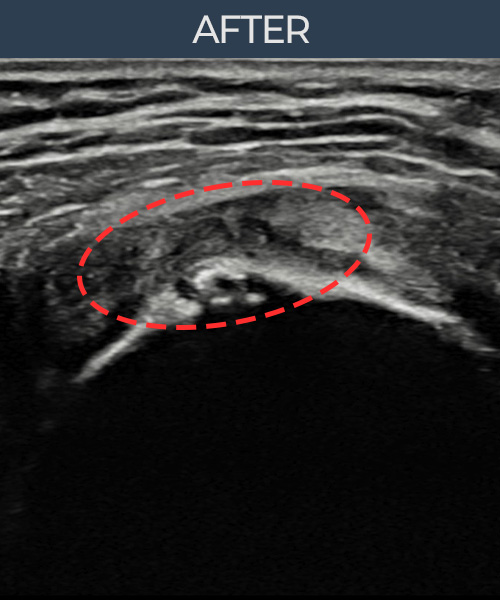

수천건의 수술 경험을 바탕으로 정확히 진단하여

인대파열을 비수술로 치료합니다.

플래티넘정형외과에서는 수술이 필요없는 인대파열만을

정확히 진단하여 특허받은 술기로 비수술로 치료합니다.